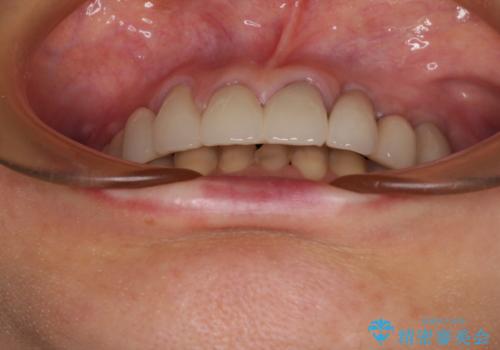

上顎はほぼ全ての歯をセラミッククラウンにて補綴治療を行う必要があるため、気になるデコボコや深い咬み合わせを改善するために下顎と上顎の臼歯部の矯正治療を行うこととしました。

並行して左下にはインプラントを埋入し、矯正治療を終えると同時に補綴治療を行うこととしました。

過蓋咬合(下顎前歯が隠れてしまうほどの深い咬み合わせ)のため、スムーズに歯が動かず矯正治療に時間がかかりましたが、無事に仕上げることができました。